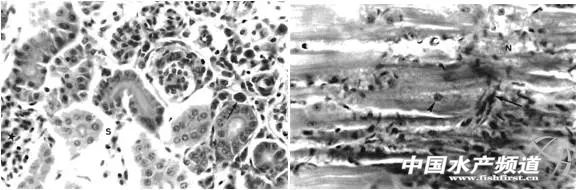

中國水產頻道報道,早在1997年,澳大利亞詹母斯庫克大學的Ariel E等研究報道了養殖羅非魚感染蛙虹彩病毒(Ranavirus)病的事件,感染病毒的羅非魚魚種于兩個月內死亡率達到100%。這給羅非魚的養殖帶來嚴重的經濟損失。 蛙虹彩病毒屬于虹彩病毒科,蛙虹彩病毒屬,病毒粒子呈二十面體,輪廓為六角形,有囊膜。大量病毒顆粒堆積可呈晶格狀排列,直徑一般為120~300 nm。蛙虹彩病毒主要感染魚類、兩棲類和爬行類動物。感染魚類包括加州鱸、石斑魚、河鱸、虹鱒等,侵襲范圍從幾克的苗種到幾百克的成魚,發病水溫在20~28℃,次高溫時發病。目前我國養殖的加州鱸、石斑魚每年都有發病病例。 該次研究首次報道蛙虹彩病毒感染羅非魚魚苗。該羅非魚養殖場采用網箱養殖方式,水溫恒定在24℃。患病魚表現出典型的旋轉性綜合征(Spinning tilapia syndrome,STS)癥狀,時而在水體中呈螺旋狀快速游動,時而停止在水底,時而呈45°懸掛在水面。感染病毒的羅非魚呈現體色發黑、鰓絲蒼白、眼球突出和腹水癥狀,有些魚頜下皮膚出現紅斑,內臟器官尤其是肝臟明顯發白,脾臟、腎臟和心臟出現嚴重的出血性壞死,繼而形成壞疽,腎小管收縮,腎間質出血并伴有大量炎性細胞浸潤,大多數肌肉出現灶性溶解(如圖標識所示)。蛙病毒不但可以通過垂直傳播途徑,還可以通過水平傳播途徑感染健康羅非魚,將具有明顯STS癥狀的羅非魚置于健康魚群中,發現健康魚逐漸出現STS癥狀,一個月內病魚死亡率約20%。 對于羅非魚感染蛙虹彩病毒病的診斷,可以通過典型的旋轉性綜合征初步判斷,但由于病毒感染后對機體產生免疫抑制作用,很快會誘發一些條件致病菌感染,所以只靠臨床癥狀診斷不夠準確。特別是該病的打轉、鰓絲貧血、眼球突出、腹水等癥狀與目前高發的羅非魚鏈球菌十分相似,容易誤診。進一步的確診還要通過流行病學調查、PCR病毒檢測、細菌分離培養等措施。采用分子生物學方法,如PCR法和LAMP法,是最為準確和特異的診斷措施。 |